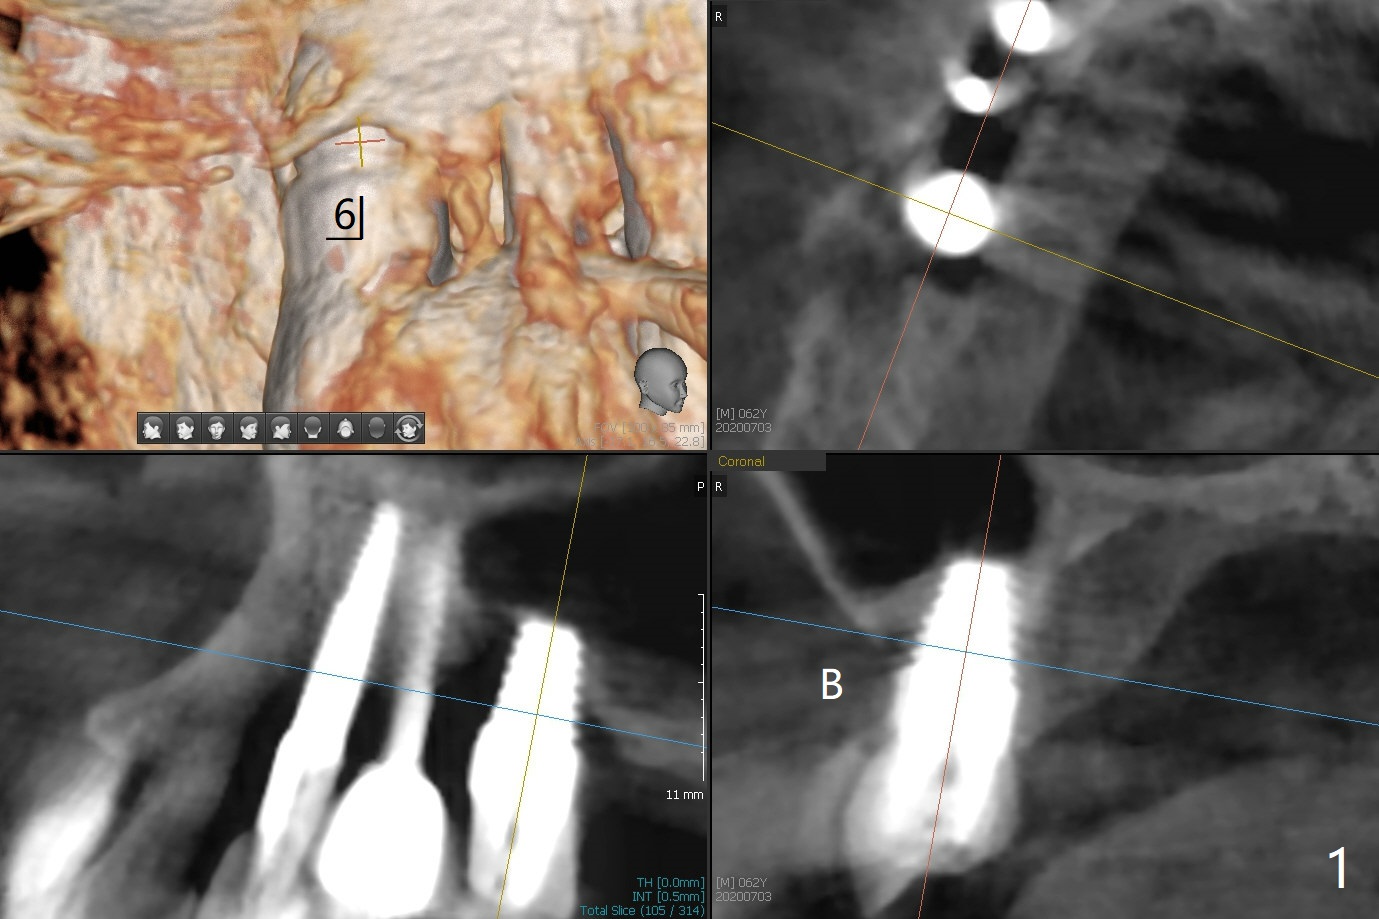

A 62-year-old man appears to have developed periimplantitis at UR6 (6x11 mm, 7 years 8 months post cementation, bone graft x3). Prepare PRFx2, Titanium brush, Tatum implant and abutment drivers in case of removal. Take photos to show erythema of the buccal gingiva before surgery (1).